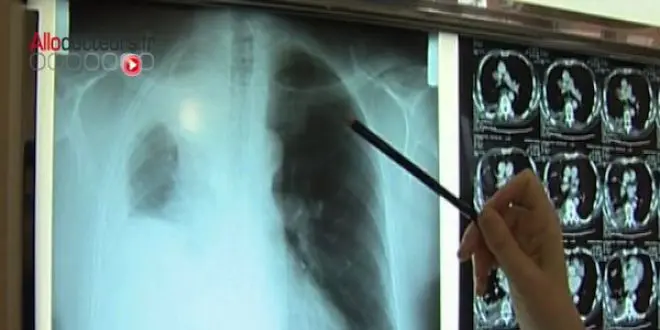

En France, l'amiante est jugée responsable de 10% à 20% des cancers du poumon et devrait être responsable de 100 000 morts d'ici 2025, selon les autorités sanitaires.

Son caractère cancérigène est connu depuis les années 1950 mais le premier décret réglementant son usage ne date que de 1977. Les premières plaintes pénales de travailleurs exposés à l'amiante datent de 1996.